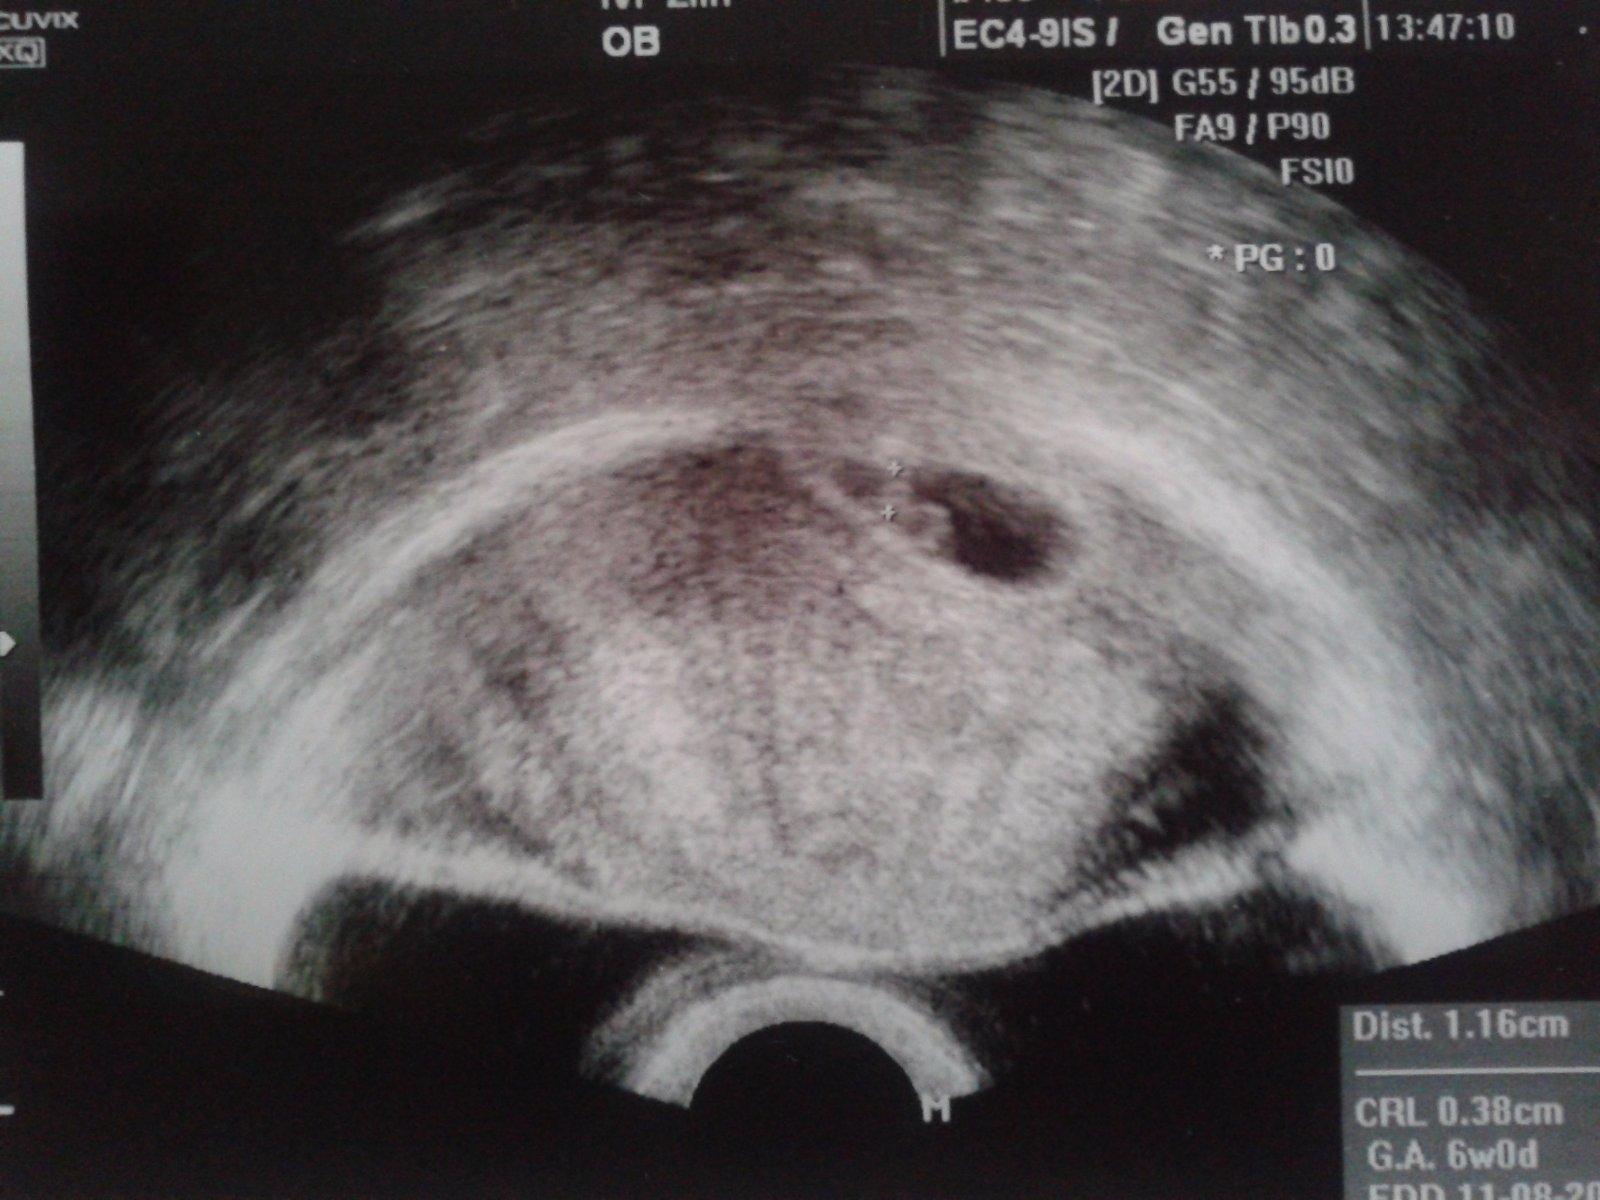

Tak dnes kontrola a paní doktorka mi vzala krev za hodinu a půl byly výsledky, pozitivní a na ultrazvuku 2 milimetry velká bublinka, no neuvěřitelné. Další kontrola za týden 🙂 Tak teď, aby to všechno šlo správně a pokračovalo.

Ahoj děvčata, tak jsem byla ve čtvrtek na kontrole a už paní doktorka viděla bijící srdíčko, tak snad bude i nadále vše jak má 🙂 Přeji vám všem, aby se vám sen o miminku v nadcházejícím roce vyplnil. Neztrácejte naději, zkuste být pozitivně naladěné a užívat si toho co máte, to jsem praktikovala na sobě, když mi bylo smutno, říkala jsem si: Raduj se z toho co máš ....a nemysli nad tím co ne, stejně je to osud, buď to bude nebo ne...Přidávám fotečku 🙂